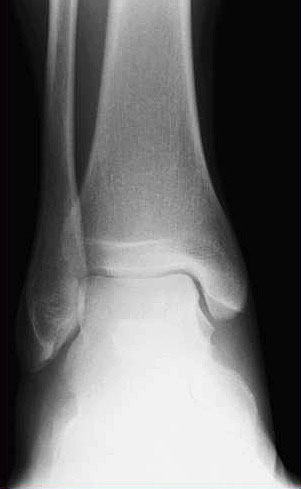

Neben der klinischen Untersuchung (Schwellung, Druck- und Klopfschmerz, Berührungsempfindlichkeit) sind Röntgenuntersuchungen obligat, obwohl sie gerade in den ersten Wochen der Erkrankung kein Korrelat bieten, aber zur differentialdiagnostischen Abgrenzung dienen. Im weiteren Krankheitsverlauf  zeigt sich nach Wochen und Monaten im Röntgen und im CT eine Osteopenie  in der betroffenen Region 8119 (Abb. 4 und 5)